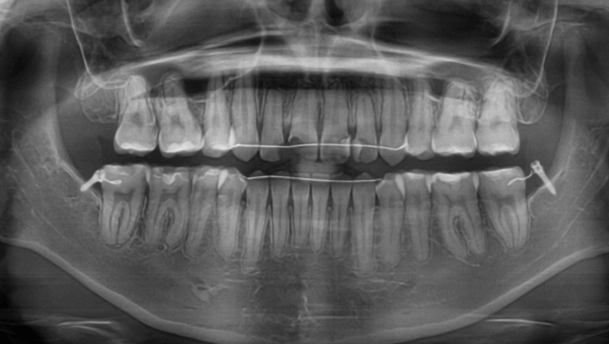

咬み合わせが逆であること(反対咬合)が気になる

| 年齢・性別 | 15歳 女性 |

|---|---|

| 主訴 | 咬み合わせが逆であること(反対咬合)を気にされて来院された女性。見た目や機能面の改善を希望されていました。 |

| 治療期間・回数 | 4年4ヶ月・28回 |

| 費用 | 900,000円 |